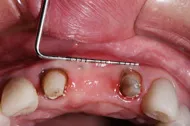

■治療前

■歯の根の引き上げ

■治療後

治療のポイント

歯の根の位置を引き上げ、抜歯。その日にインプラント治療へ。

自然の歯と変わらない審美性を取り戻し、非常に満足されています。

| 主訴 | 上顎の真ん中の歯が折れた |

| 治療方法 | 歯の根を引き上げることにより、増骨するので、その後1本のインプラントを埋入し治療した |

| 治療期間 | 約1年 |

| 通院回数等 | 10回 |

| 費用 | 550,000円(税込) |

| リスク・副作用 | 外科治療なしで増骨させた為、治療期間が長くなった |